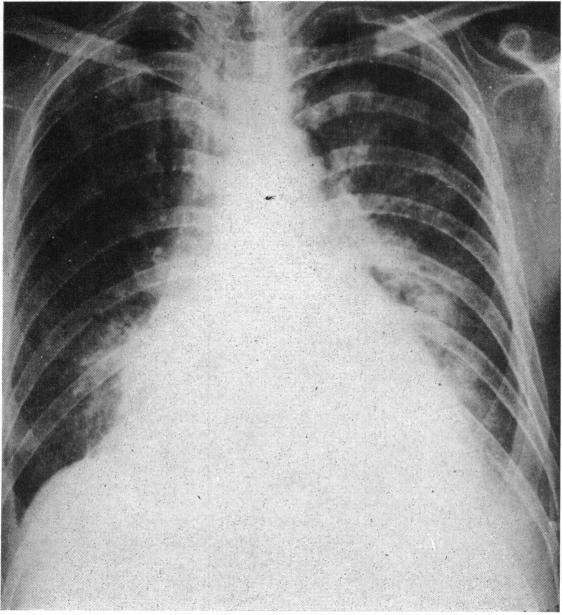

Adult heart disease due to the Coxsackie virus group B.

Br Heart J. 1966 Mar;28(2):204-20. doi: 10.1136/hrt.28.2.204.